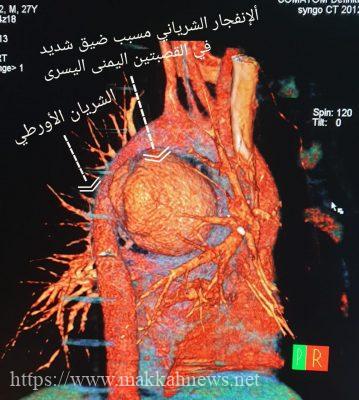

و أوضح رئيس وحده جراحة الأوعية الدموية و التداخلية الدكتور محمد القرني بأنه بعد الاطلاع على التاريخ المرضي تبين معانات المريض مع البلع قد امتدت على مدار ٣٠ يوم إلى أن تطورت و بشكل مفاجئ بألم حاد في الصدر مع صعوبة في التنفس و عدم القدرة على بلع الماء مع نوبات لفقدان الوعي. حينها قام بمراجعة احد مستشفيات مدينة جدة الحكومية ومن ثم قبول الحالة بشكل عاجل بالمدينة الطبية. تم اخضاع المريض لعدد من الفحوصات والاشعات اللازمة والتي أظهرت نتائجها وجود تسرب دموي حاد في جدار الشريان الأبهر مع تكون كتله دموية ضاغطه على القلب و القصبات الهوائية و كذلك مجرى الطعام.

و قام الفريق الطبي المكون من جراحة الأوعية الدموية يتضمن د. محمد القرني، د. أيمن السيد، د. السيد عبدالله و د. شريف مخلص و من جراحة القلب د. النذير عبدالله، ومن التخدير د. أماني بإستعراض الحالة ووضع الإستراتيجية المناسبة لها و ذلك عن طريق إجراء القسطرة عن طريق الفخذ بدون جراحة لإيقاف التسرب الدموي والاستعانة بجهاز الإكمو (الرئة الصناعية).